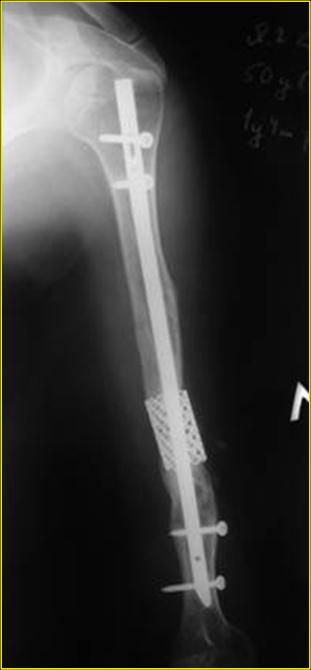

Типичная положительная ситуация для интрамедуллярного остеосинтеза с

использованием опорного металлокаркаса для компенсации дефекта.

Рентгеновская версия реконструкции. хронология:

после операции, 2 мес. после операции, через 1 год

Движения в полном объеме восстановлены к 2 мес. после операции. Если надо могу показать мультик. Сейчас уже прошло более 3 лет, больная не